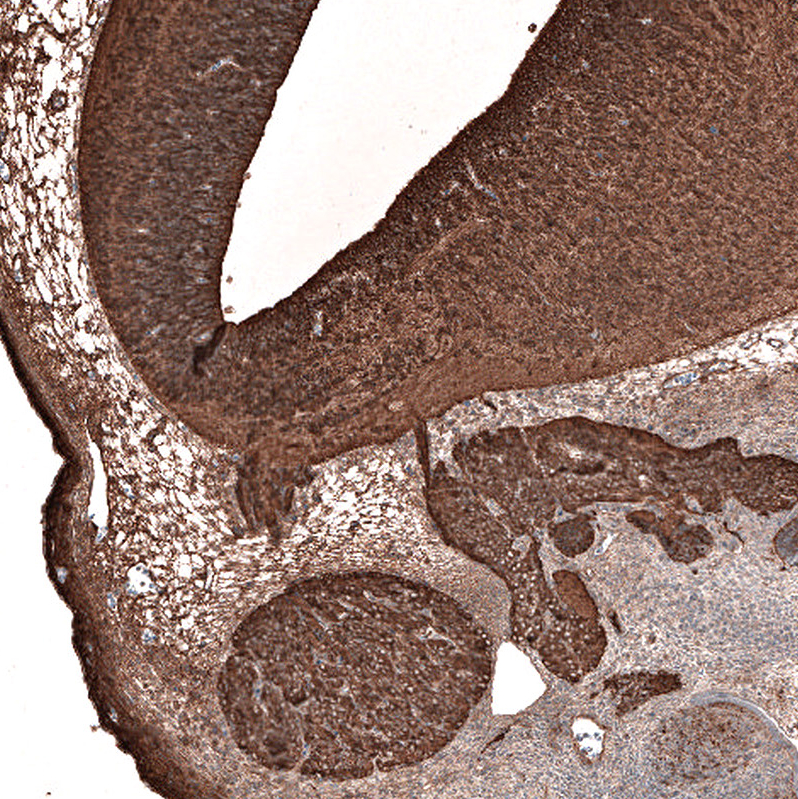

Immunohistochemistry analysis in human cerebral cortex and skeletal muscle tissues using AMAb91394 antibody. Corresponding TUBB3 RNA-seq data are presented for the same tissues.